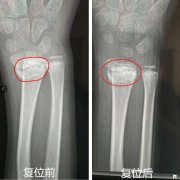

人民网重庆1月8日电 本来以为复位后就好了,没想到过了一段时间再次错位,还越来越严重,当地医院都说时...[详细]